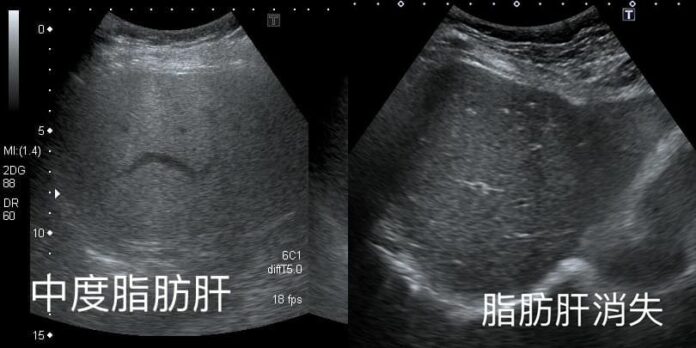

台湾胃肠肝胆科医师钱政弘分享,一名60多岁的女子日前来看诊,超音波扫描后发现,原先的中度脂肪肝已完全消失,于是开口请教对方减重的秘诀,没想到对方说出6个字,让他感到十分不可思议,仔细谘询后才发现背后的原因。

钱政弘在脸书上分享,他日前替这名阿姨做超音波检查,发现去年的中度脂肪肝已消失,这次的检查结果完全正常,开口询问以后,才知道阿姨在一年内瘦了快10公斤。